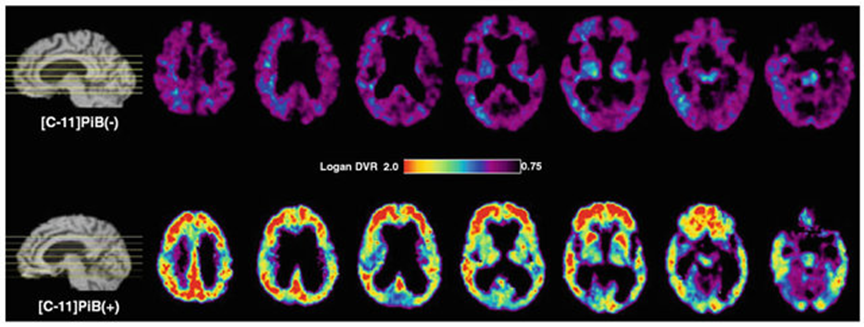

第二常見之神經退化性疾病―帕金森氏症—目前仍不清楚其發病機制。大部分研究指出病患的動作行為障礙主要與腦部負責產生多巴胺之特定神經元功能退化有關,因此,針對該疾病之的診斷及治療大多數皆以多巴胺的供給為主要標的。然而,造成該病患腦部多巴胺神經元持續衰亡的原因仍然不明。為了探索該病可能的致病病因、致病機轉以及篩選可能可阻止多巴胺神經元退化之藥物,許多研究團隊以神經毒劑於實驗動物中誘發多巴胺神經凋亡退化以製造帕金森氏症模型,並結合可針對多巴胺神經元上特定蛋白之放射性示蹤劑進行長期之活體觀察,希望可以找到誘發帕金森氏症的病理機制。本研究團隊先前採用可結合至多巴胺前突觸神經元內之第二型單胺囊泡轉運子之放射性正子示蹤劑 (18F-FP-(+)-DTBZ),分別使用於以神經毒劑 MPTP 或 6-OHDA 製造帕金森氏症動物模型,結果可明顯地觀察到這兩種神經毒劑造成多巴胺神經元損傷(圖二)。

以正子斷層造影影像觀察實驗動物中使用18F-FP-(+)-DTBZ追蹤於神經毒劑MPTP 6-OHDA(右圖)處理後多巴胺代謝狀況

圖二、以正子斷層造影影像觀察實驗動物中使用18F-FP-(+)-DTBZ追蹤於神經毒劑MPTP(左圖)或6-OHDA(右圖)處理後多巴胺代謝狀況